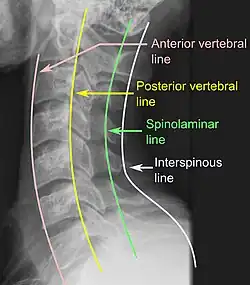

Na tomografia computadorizada ou radiografia, uma fratura cervical pode ser visualizada diretamente. Além disso, sinais indiretos de lesão pela coluna vertebral são incongruências das linhas vertebrais,[6] e/ou aumento da espessura do espaço pré-vertebral:[7]